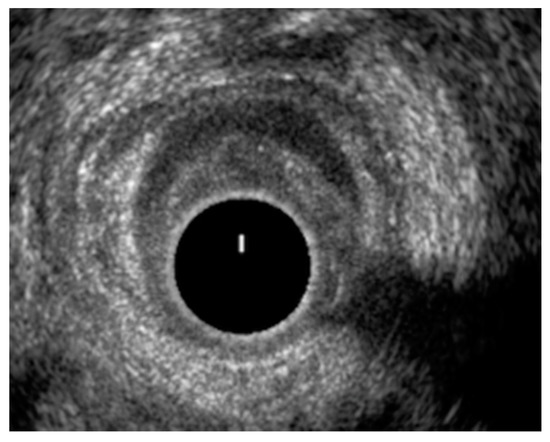

3.3. High-Resolution Anorectal Manometry and Balloon Expulsion Test